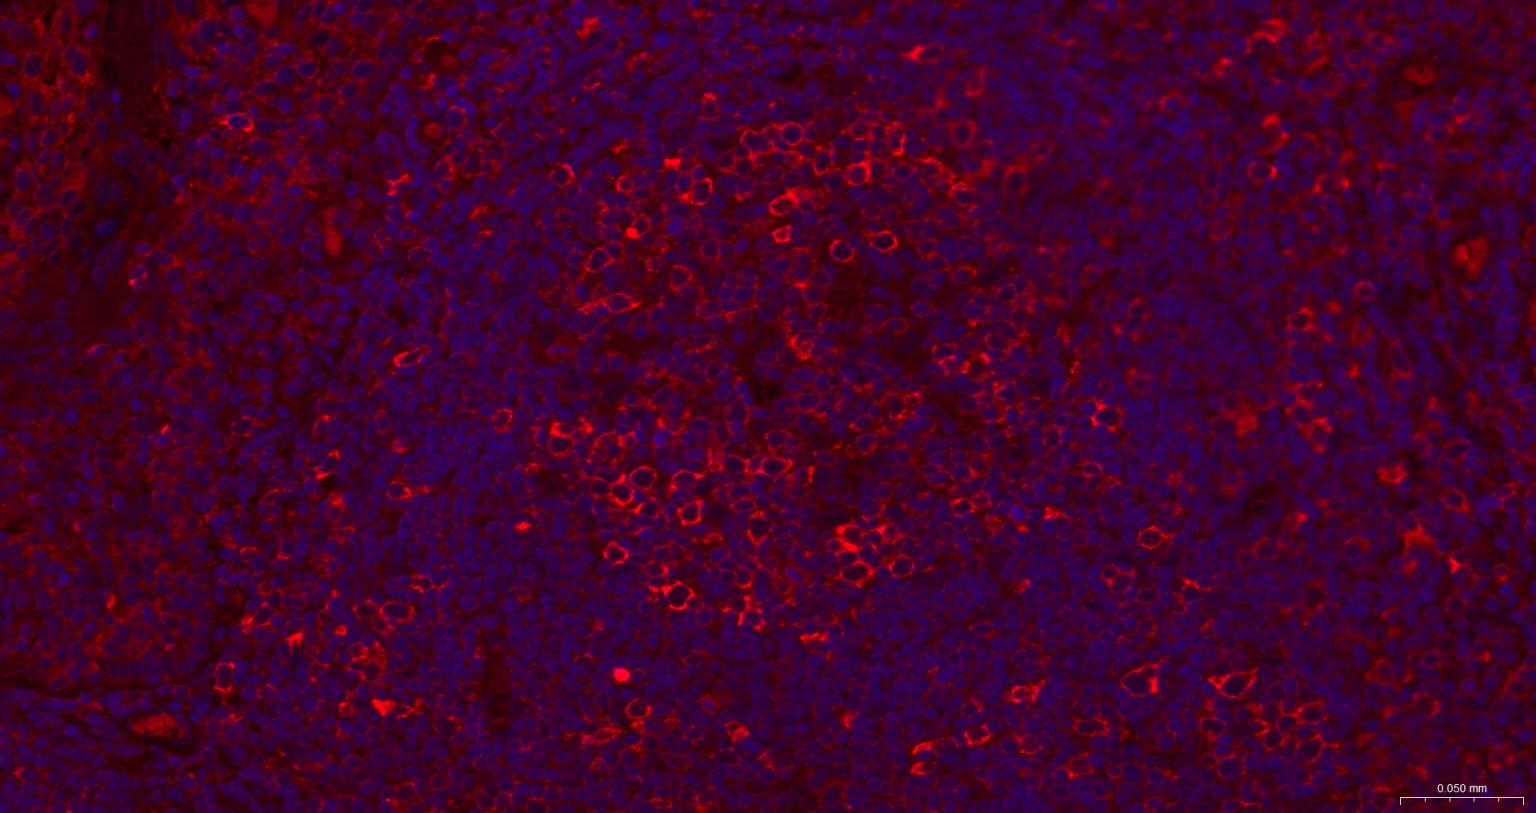

| IF | Human, Mouse, Rat | 1:100-500 | |

| ICC/IF | Human, Mouse, Rat | 1:50-200 |